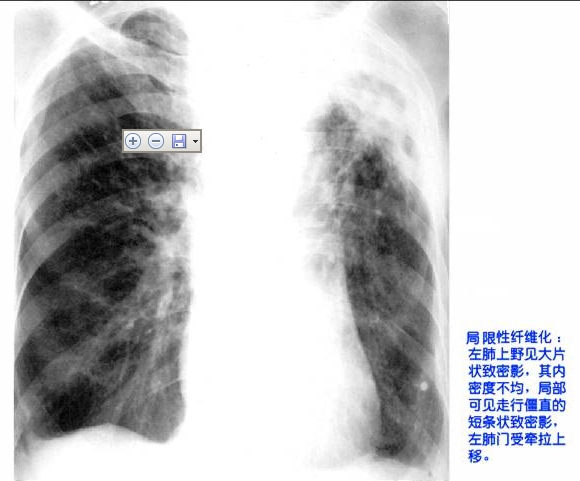

照片名称:局限性纤维化